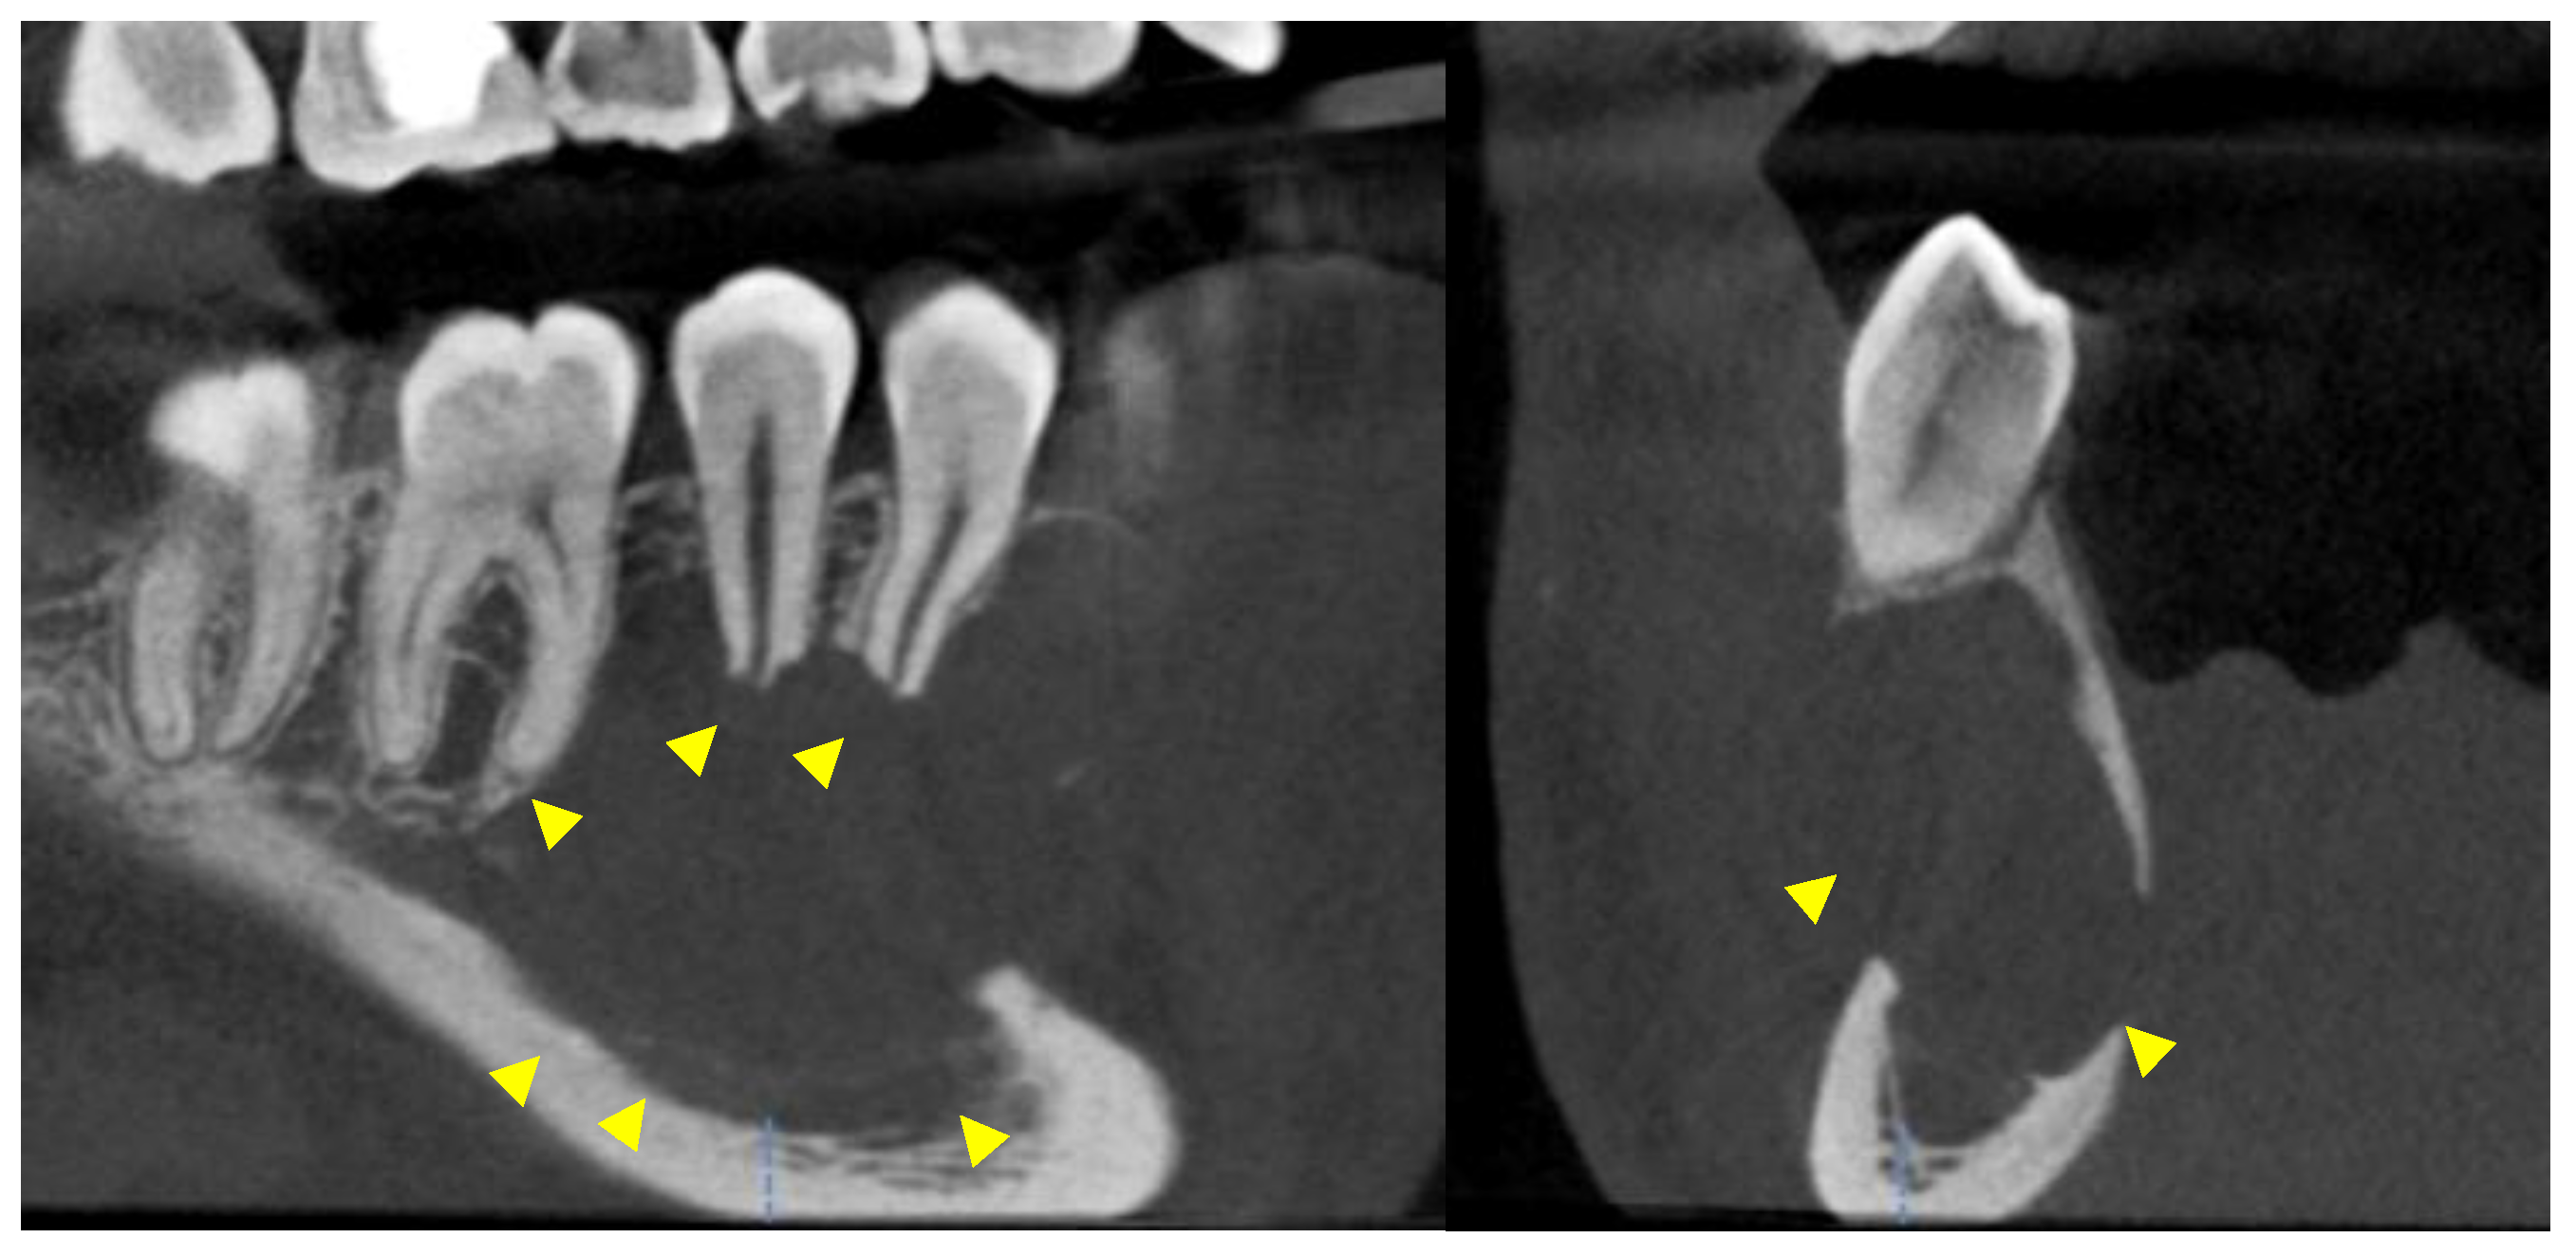

Further investigation with a cone-beam computed tomography (CBCT) was scheduled and a scan was acquired using DENTSPLY Sirona© XG3D with a Field Of View (FOV) of 8 cm width and 5 cm height. The exposure settings were set at 85 kilovoltage peak (kVp), 6 milliamperes (mA), and 14.179 s (sec). The scan confirmed the presence of a moderate to large entity in the right posterior mandible. Mesiodistally, the entity extended from the distal aspect of the root of #27 to the mesial aspect of the mesial root of #30. It extended from the level of the alveolar crest and the apical half of the roots of the aforementioned teeth to a few millimeters superior to the inferior cortical border of the mandible. Bucco-lingually, the entity covered the entire width of the mandible. The entity was well defined, unilocular, and partially corticated, with evidence of scalloping between the roots of teeth #27, 28, 29, and #30. Evidence of interruption of the lamina dura and moderate root resorption was noted in the apical half of the roots of the associated teeth. Non-uniform thinning, expansion, and interruption of the buccal and lingual cortices were detected and the inferior alveolar canal was interrupted and inferiorly displaced (Figure 3, Figure 4 and Figure 5).

Figure 3. Oblique sagittal views on a CBCT study. The yellow arrowheads show evidence of root resorption and scalloping between the roots of the involved teeth.

Figure 4. Oblique sagittal and cross-sectional views on a CBCT study. The yellow arrowheads point to the interruption of the lamina dura, the inferior displacement of the inferior alveolar canal, and the thinning/expansion/interruption of the buccal and lingual cortices.